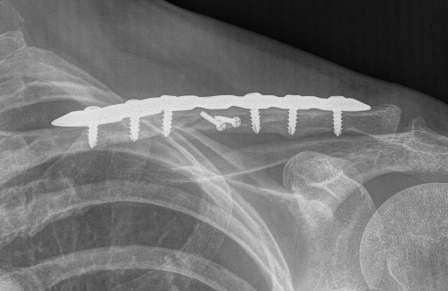

Shorted / displaced midshaft clavicle fractures

Plate fixation of shorted displaced midshaft clavicle fractures reduces nonunion rates

Plate fixation

Superior versus anteroinferior plates